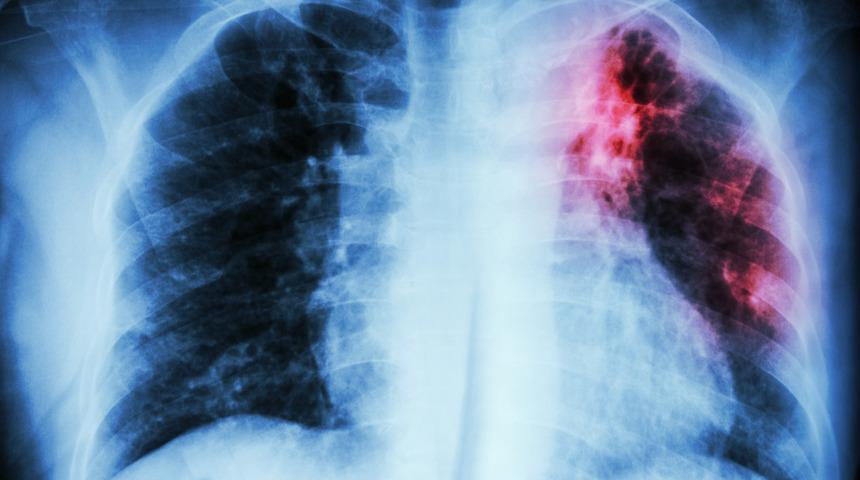

Güney Kore'de korkutan hastalık: Yeni bir zatürre (pnömoni) türü olabilir

Güney Kore'de zatürreye (pnömoni) benzetilen 'gizemli solunum yolu hastalığı' hastalığı nedeniyle bir kişi karantinaya alındı. Hastanede tedavi edilen kadının yaşadığı hastalığın nedeni henüz belirlenemedi. İşte dünyada paniğe neden olan o olayın detayları...

Hong Konglu yetkililer de yeni bir zatürre türü olduğu sanılan hastalığın geçen aydan bu yana 15 kişide görüldüğünü duyurmuştu. (AA)